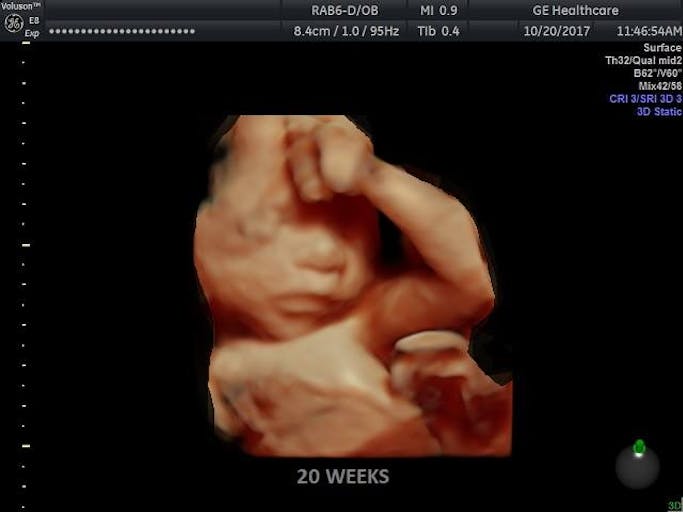

Mississippi House passes bill banning abortion after 20 weeks in 89-22 vote

A bill banning abortions beyond 20 weeks has passed the Mississippi House and now makes its way to the Senate, offering hope for life for Mississippi babies aborted even beyond viability.